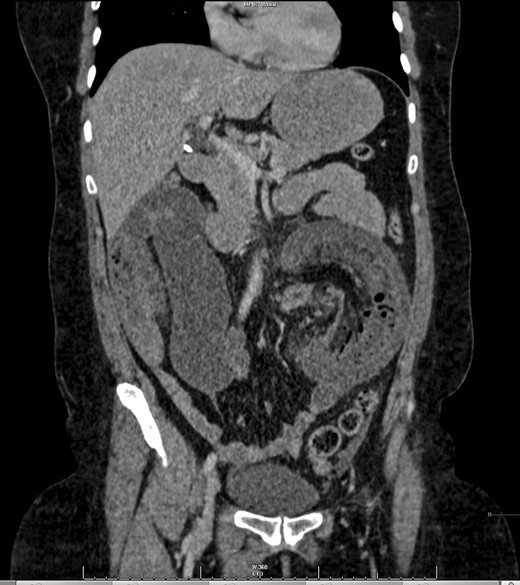

A 47-year-old female presented as an emergency with severe abdominal pain and profuse vomiting. She had been experiencing symptoms of intermittent vague abdominal pain associated with weight loss over 6 months, but no change in bowel habit. She had no significant past medical history. On examination she was tachycardiac, pyrexial and abdominal examination revealed distended abdomen with localized tenderness in the left iliac fossa. Blood tests revealed an elevated white cell count (18.8), C-reactive protein (25), microcytic anaemia (Hb 108) and a mildly raised lactate (2.37). She was commenced on intravenous fluids. An abdominal plain film showed prominent bowel loops and ultrasound of the abdomen revealed numerous loops of a distended, fluid filled, non-peristalsing bowel. There was some evidence of bowel wall thickening, but no clear source of obstruction was identified. A CT scan was performed showing mesenteric vascular gas and a target sign, virtually pathognomonic of intussuception [5, 6] (Figs 1 and 2).

While correct diagnosis is based on operative findings, suspicion may be raised following imaging techniques. CT with both oral and intravenous contrast is now widely recognized as the most accurate diagnostic tool (58–100% accuracy in a recent case series) [1, 4]. Alternating hyper- and hypodense layers of the bowel wall of the intussuscepted segment give rise to a classical ‘target sign’ [5] (Fig. 1).